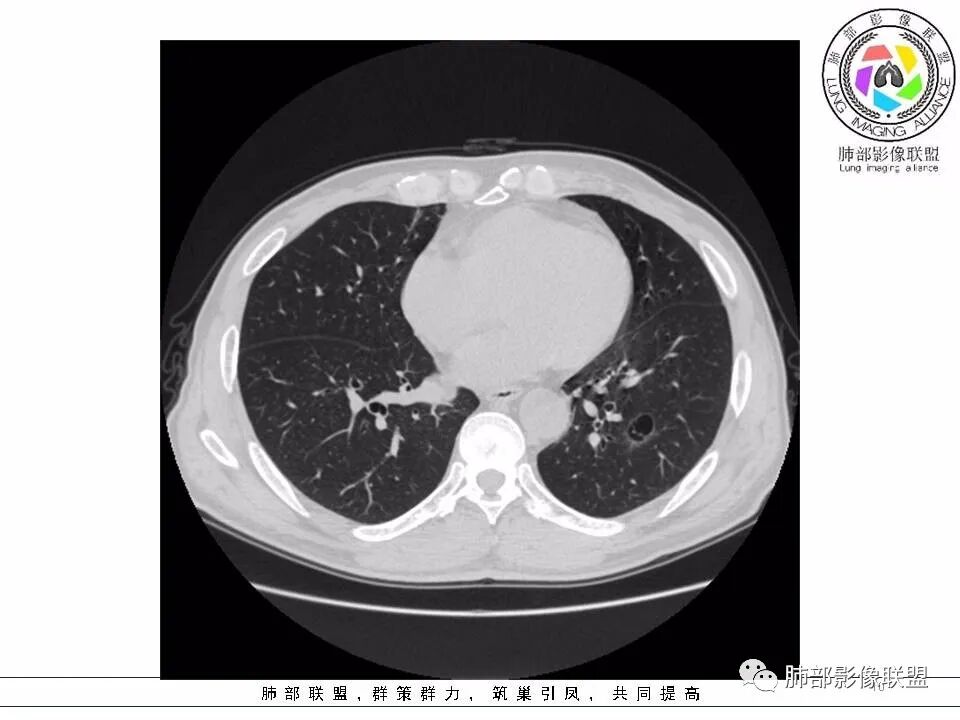

2.左肺下叶外基底段囊腔样病灶,轮廓柔和,壁厚薄不均,见壁结节。内见分隔或脊状突起。腔内见血管穿行。

这是有“故事”的囊!

3.囊壁外环以磨玻璃影,边界较清楚。

1.囊腔壁厚薄不均,壁结节,内有分隔,其内有血管穿行,指向新生物。

2.临近有边界清楚磨玻璃影,指向腺癌。